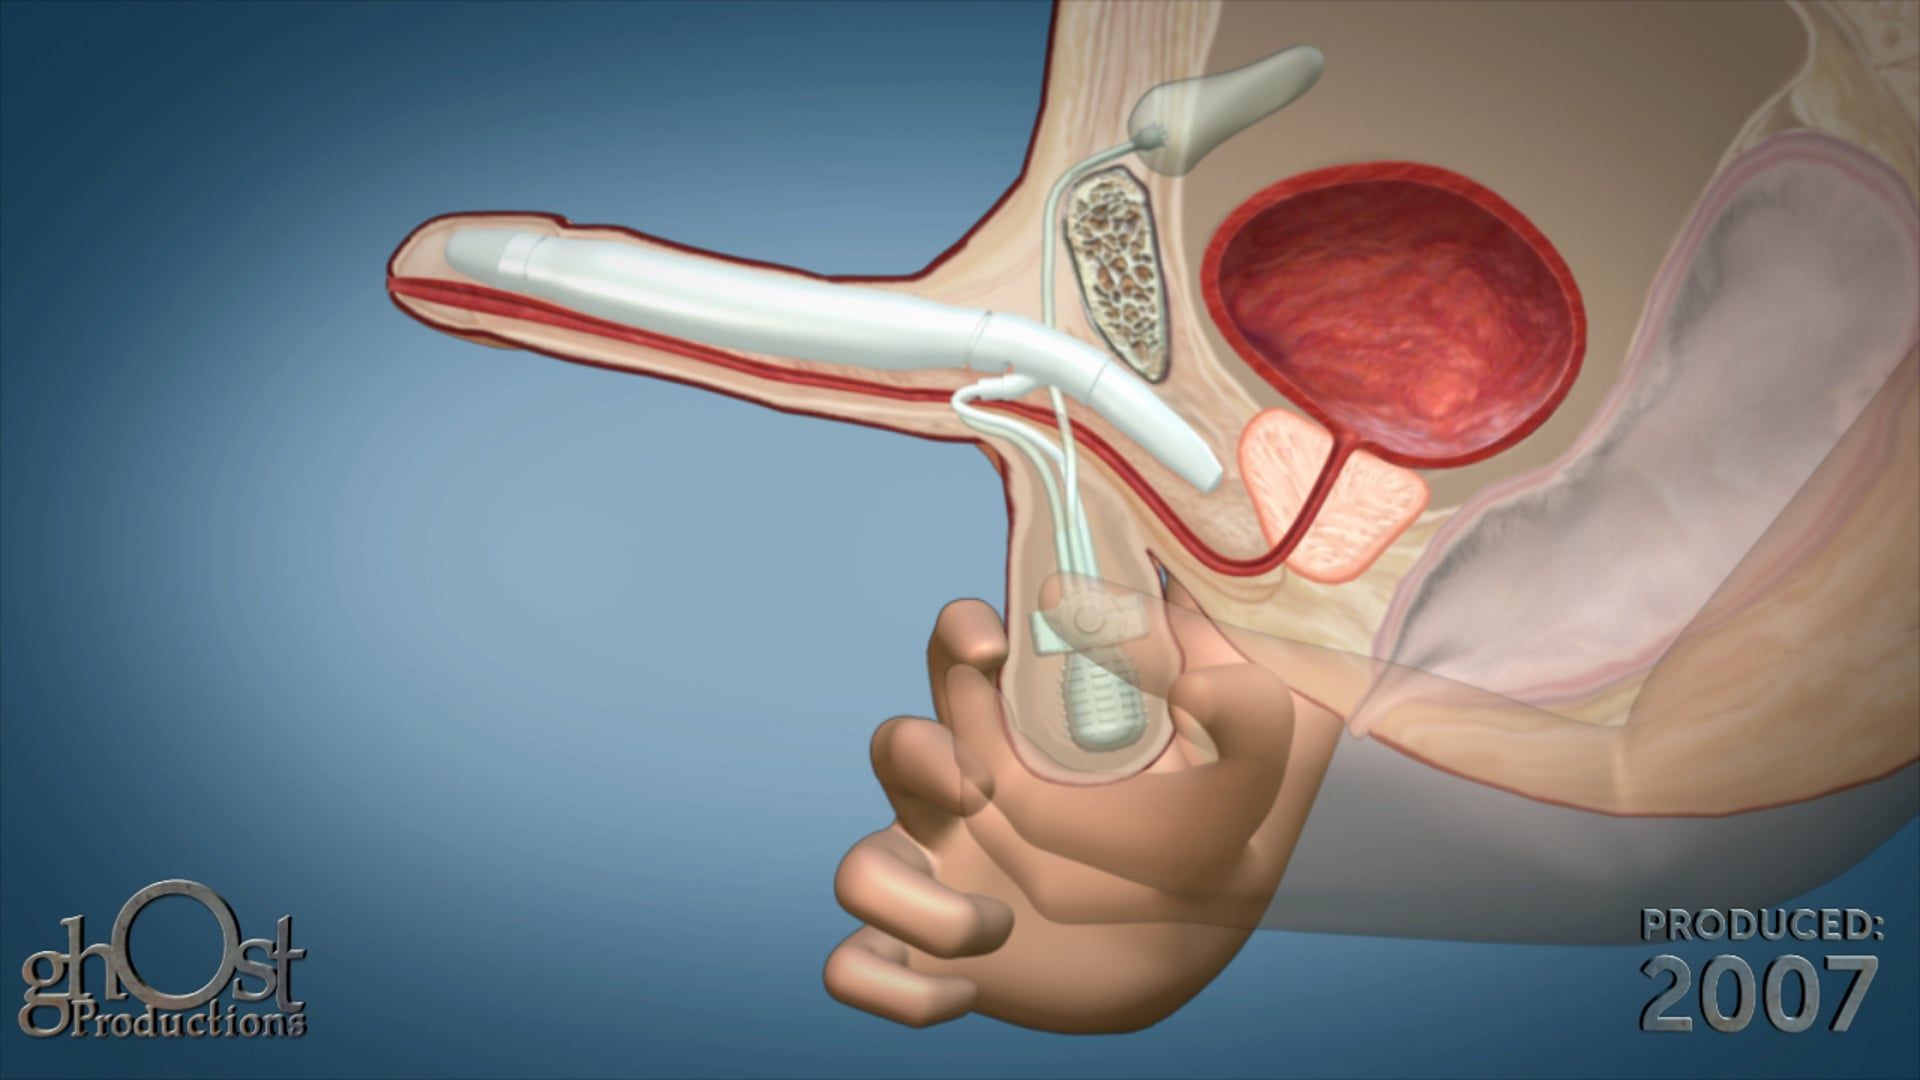

Discover the AMS Continuum, a reliable and innovative bladder anchored urinary catheter with retractable tines, through this stunning animation.

Looking for a reliable and effective bladder anchored urinary catheter with retractable tines? Look no further than the AMS Continuum, brought to life in stunning detail in this animation from Ghost Productions. Our team worked closely with American Medical Systems to create a visual representation of this innovative medical device, highlighting its unique features and benefits. Whether you're a healthcare provider looking for the latest in urinary catheter technology or a patient seeking a more comfortable and secure solution, the AMS Continuum is a game-changer. Watch our animation today to learn more!